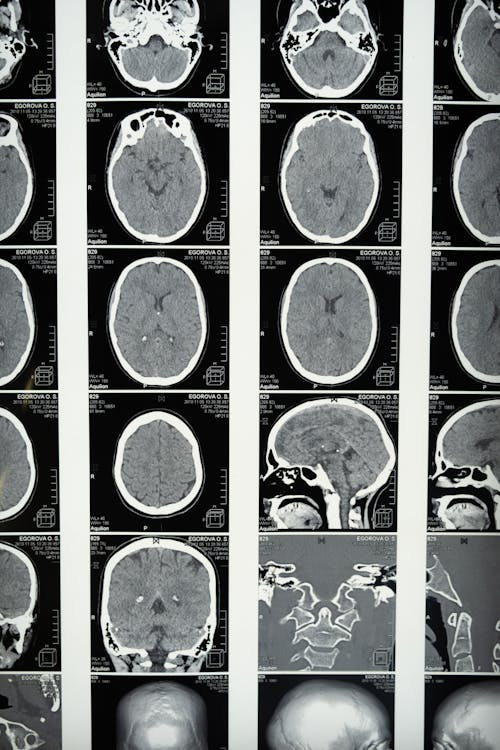

1️⃣ CT(컴퓨터단층촬영)

→ 출혈 여부를 빠르게 확인 (응급 시 필수)